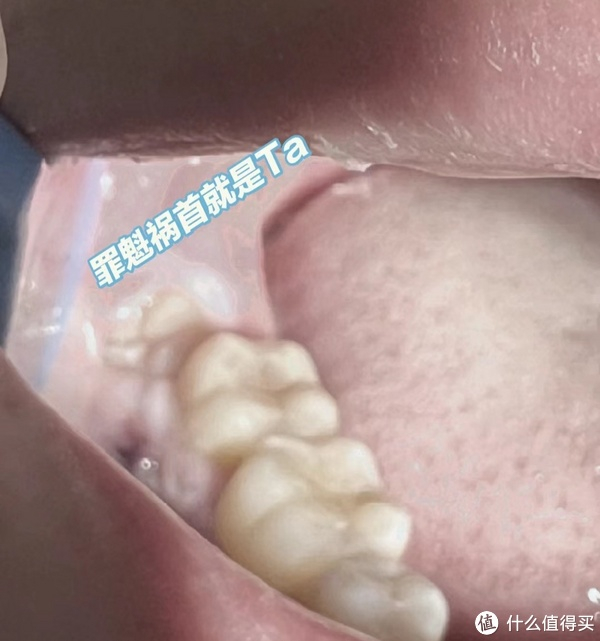

拔4颗智齿_口腔健康_什么值得买

图片尺寸864x1152